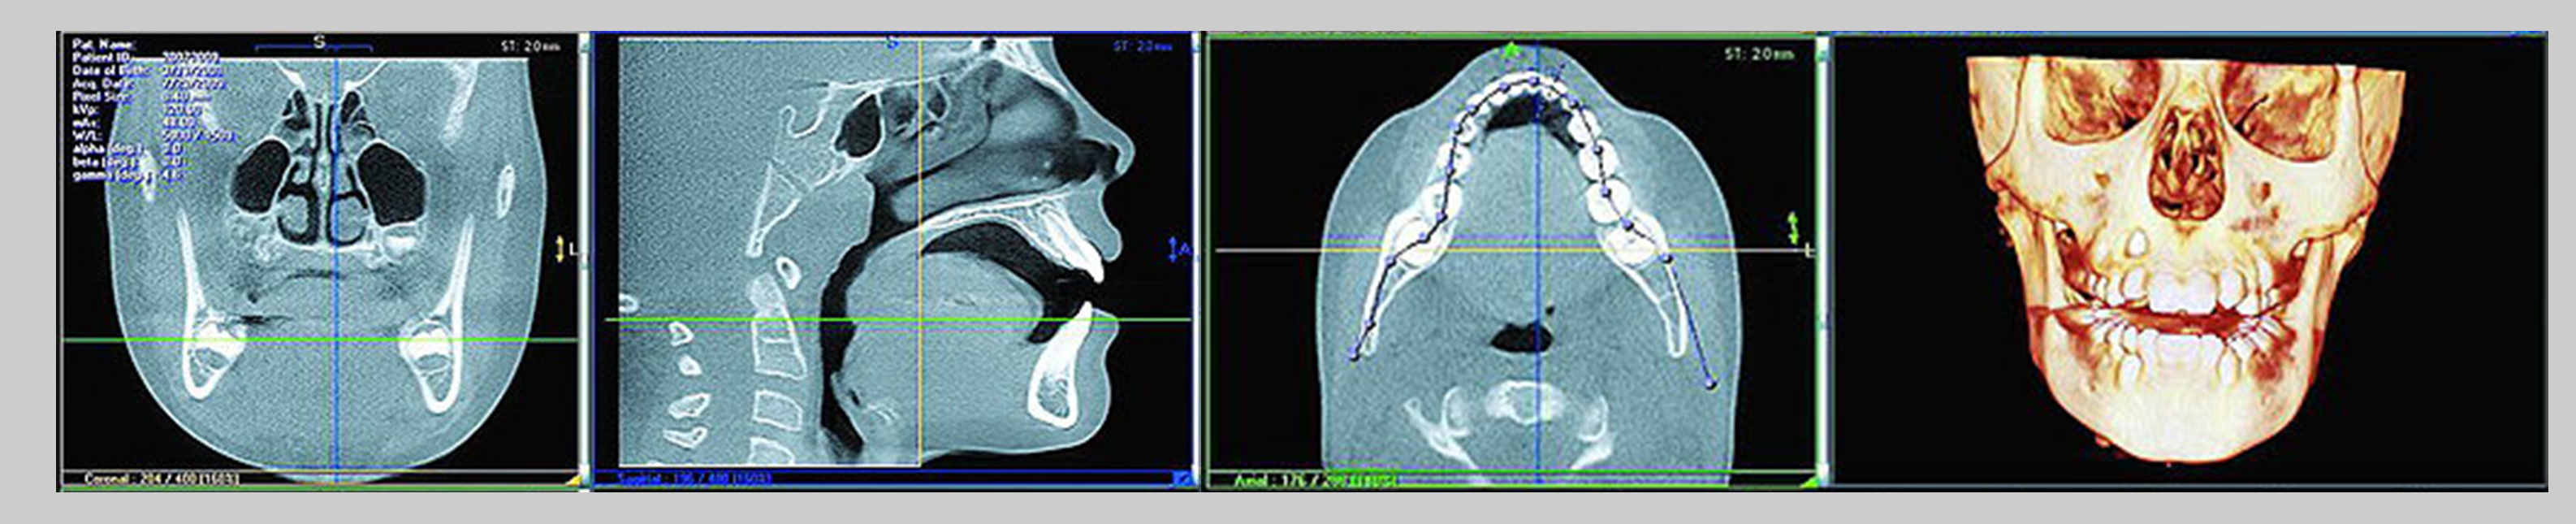

Od jednog 3D snimka moguće je proizvesti bilo koji broj visoko kvalitetnih preseka: panoramskih, aksijalnih, transverzalnih, poprečnih, sagitalnih, kosih i trodimenzionalnih, a sve to samo sa nekoliko klikova mišem. Debljina svakog snimka tj. preseka može se podesiti prema vlastitoj želji. Tako ste u mogućnosti videti bilo koju kombinaciju preseka.

Povezani smo sa Rtg centrom i na taj način istovremeno sa izradom kompjuterizovanog tomografskog 3D snimka omogućena nam je analiza i postavljanje dijagnoze (možemo da vizualizujemo u trodimenzionalnom prostoru gdje se može smjestiti implant, da li ima dovoljno kosti kao i kako izbjeći strukture kao što su nervi i krvni sudovi).